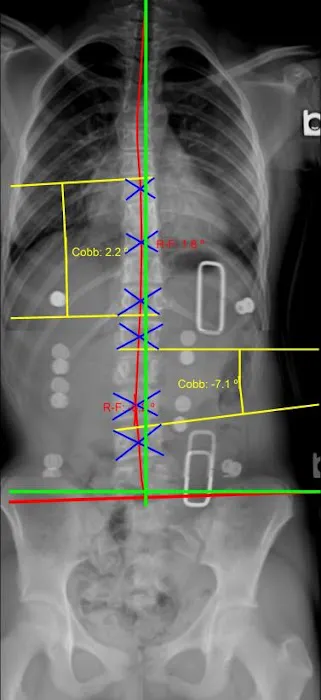

- Scoliosis Management: The center has experience in managing conditions like scoliosis, helping patients who may not have realized they had the condition for most of their lives. Treatment aims to alleviate associated pain and improve spinal health.